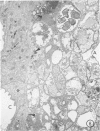

In order to characterize the alveolar response to Pneumocystis carinii pneumonia, light and electron miscropy were used to trace the development of experimental infections with P carinii in rats treated with cortisone acetate and a low-protein diet. The first changes were found by the eighth day of treatment and consisted of the selective attachment of Pneumocystis organisms, mostly trophozoites, to alveolar Type 1 pneumocytes; the host cells were undamaged, and no inflammatory response was seen. After approximately one month of treatment, the seemingly innocuous host-parasite interaction was succeeded by focal necrosis of the Type 1 pneumocytes adjacent to organisms; hyperplasia of nearby Type 2 pneumocytes also occurred, to replace the dead Type 1 pneumocytes. Even at this stage, inflammatory reaction was conspicuously absent except for occasional alveolar macrophages in the diseased alveoli; in addition, all cells of the alveolar-capillary membrane other than Type 1 pneumocytes appeared entirely normal. Not only does the present study clarify the nature of alveolar injury caused by Pneumocystis carinii, but it also provides an experimental animal model in which selective injury of the alveolar lining cells occurs.